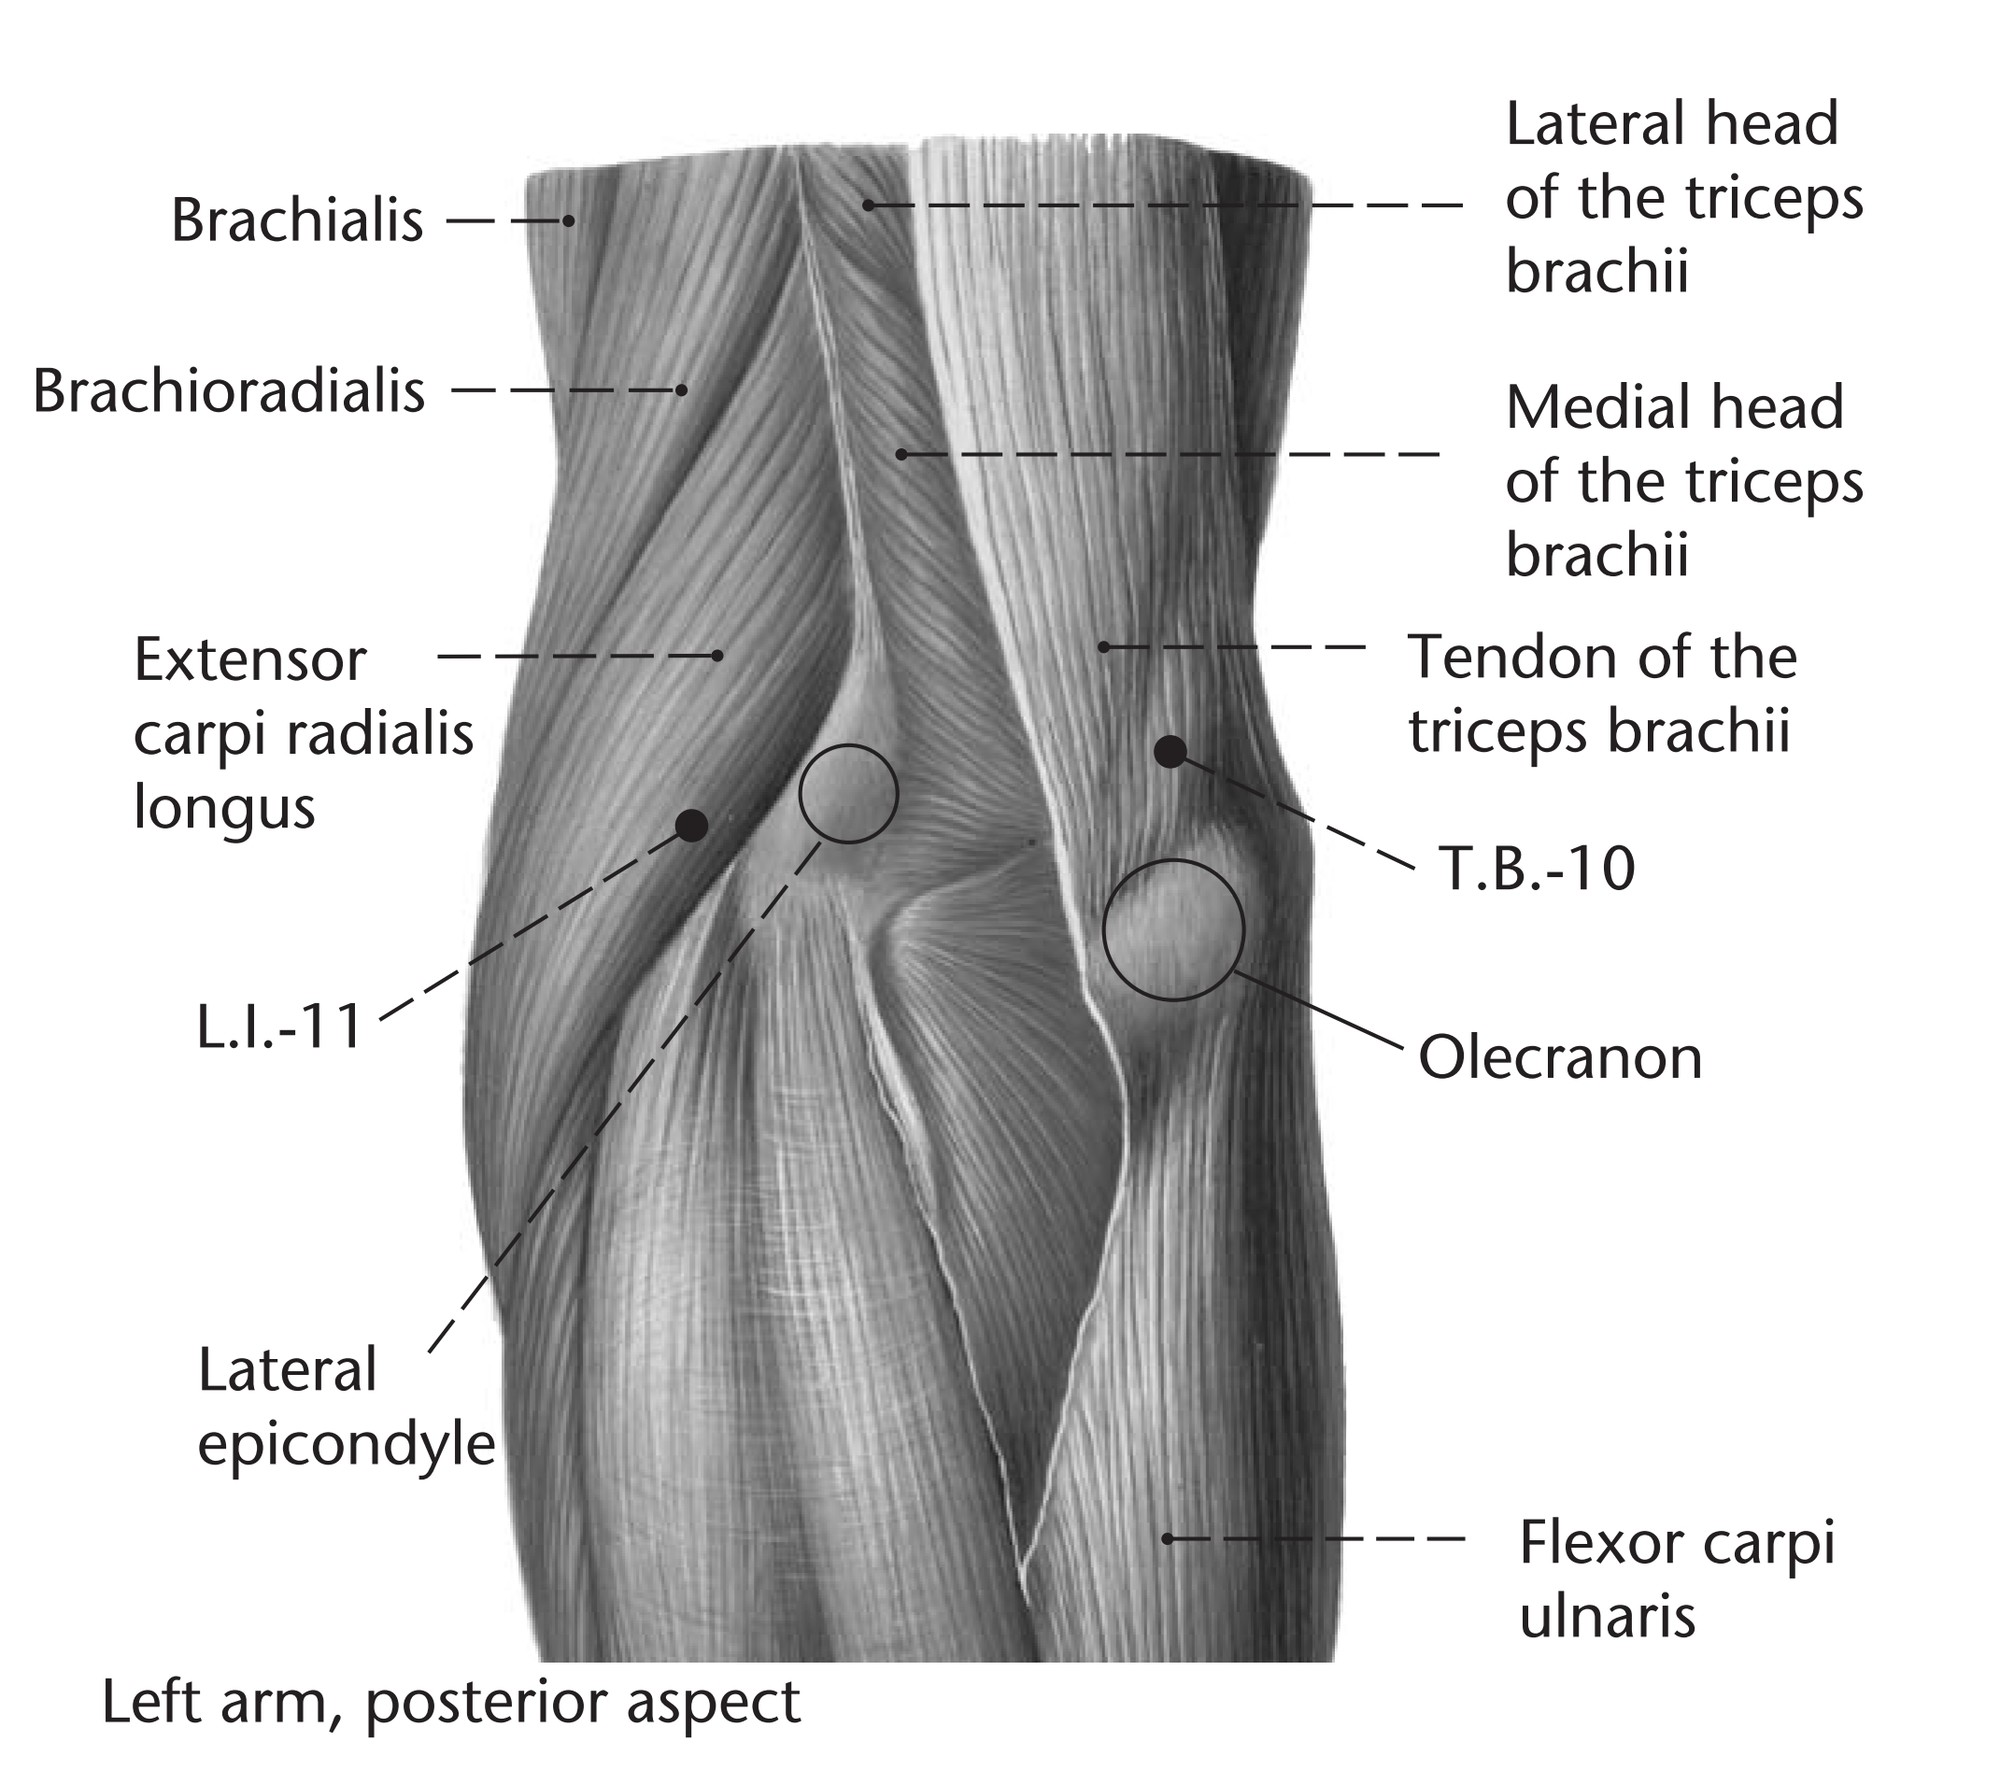

Анатомия и функции мышцы brachioradialis